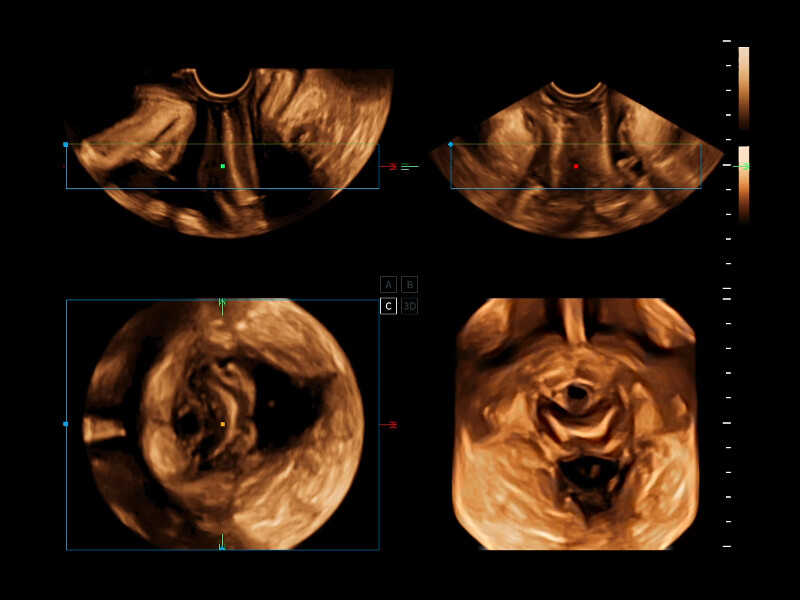

S-Live Contour

S-Live Studio

S-Fetus 5.0

STIC